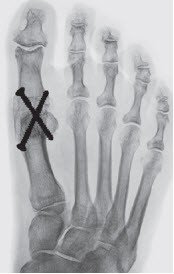

Ziel der Chirurgie ist die möglichst exakte Wiederherstellung einer normalen Anatomie, wie sie vor dem Auftreten der Deformität bestanden hat. Der schräg stehende Mittelfussknochen, der nach innen drückt, muss also aufgerichtet und in der korrekten Stellung stabilisiert werden. Die Grosszehe steht dann wieder gerade auf dem Mittelfussknochen und entfaltet ihre volle Stützfunktion, was die Überlastungsschmerzen an der Fusssohle zum Verschwinden bringt. Das bei uns am häufigsten angewandte Operationsverfahren ist die sogenannte «Scarf»-Osteotomie, die hier dargestellt wird. Diese Korrektur erfolgt durch einen Knochenschnitt (Osteotomie), der mit zwei bis drei kleinen Schrauben in der korrekten Stellung bis zur Heilung (sechs bis acht Wochen) fixiert wird. Die später funktionslos gewordenen Schrauben spürt man nicht, sie müssen nur ausnahmsweise entfernt werden.